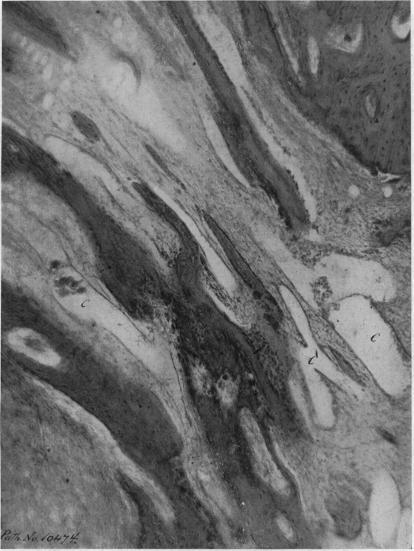

I. Benign Bone Cysts, Ostitis Fibrosa, Giant-Cell Sarcoma and Bone Aneurism of the Long Pipe Bones: A Clinical and Pathological Study with the Conclusion that Conservative Treatment is Justifiable.

Ann Surg. 1910 Aug;52(2):145-85. doi: 10.1097/00000658-191008000-00001.